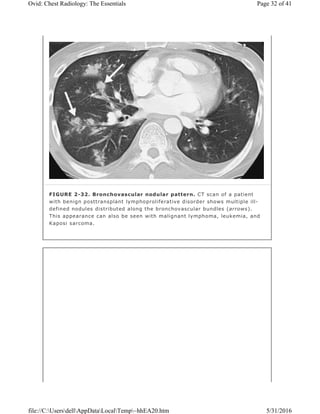

FIGURE 2-32. Bronchovascular nodular pattern. CT scan of a patient

with benign posttransplant lymphoproliferative disorder shows multiple ill-

defined nodules distributed along the bronchovascular bundles (arrows).

This appearance can also be seen with malignant lymphoma, leukemia, and

Kaposi sarcoma.

irregular nodules in a bronchovascular distribution are characteristic of benign

lymphoproliferative disorders (Fig. 2-32), lymphoma, leukemia, and Kaposi

sarcoma.